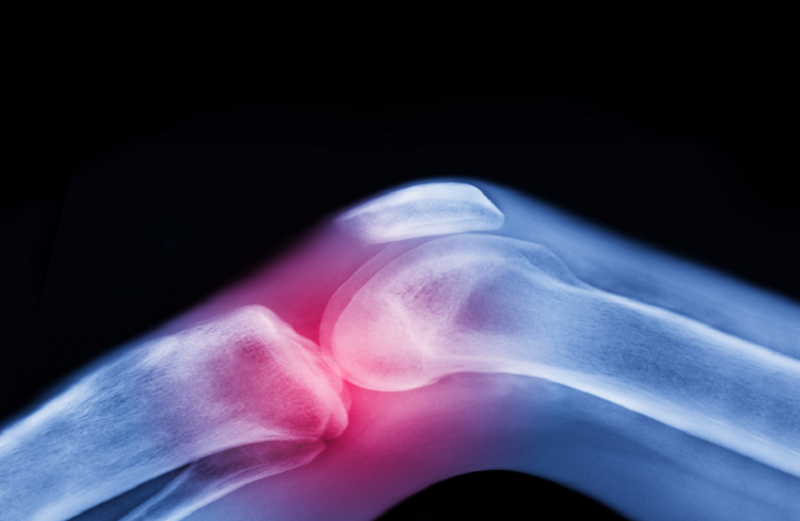

دواء شائع للسكري يخفف آلام التهاب مفاصل الركبة

وأظهرت الدراسة أن الميتفورمين، المستخدم عادة لعلاج السكري من النوع الثاني، يمكن أن يساعد في تخفيف آلام الركبة الناتجة عن هشاشة العظام لدى الأشخاص الذين يعانون من زيادة الوزن أو السمنة، ما قد يؤخر الحاجة إلى عمليات استبدال الركبة.

ووجدت الدراسة أن المرضى الذين تناولوا الميتفورمين أبلغوا عن انخفاض في شدة الألم بمقدار 31.3 نقطة على مقياس من 0 إلى 100، مقارنة بـ 18.9 نقطة فقط لدى المجموعة التي تناولت الدواء الوهمي. وأشارت النتائج إلى أن الميتفورمين يمكن أن يكون علاجا فعالا في تخفيف آلام الركبة المصاحبة لهشاشة العظام.